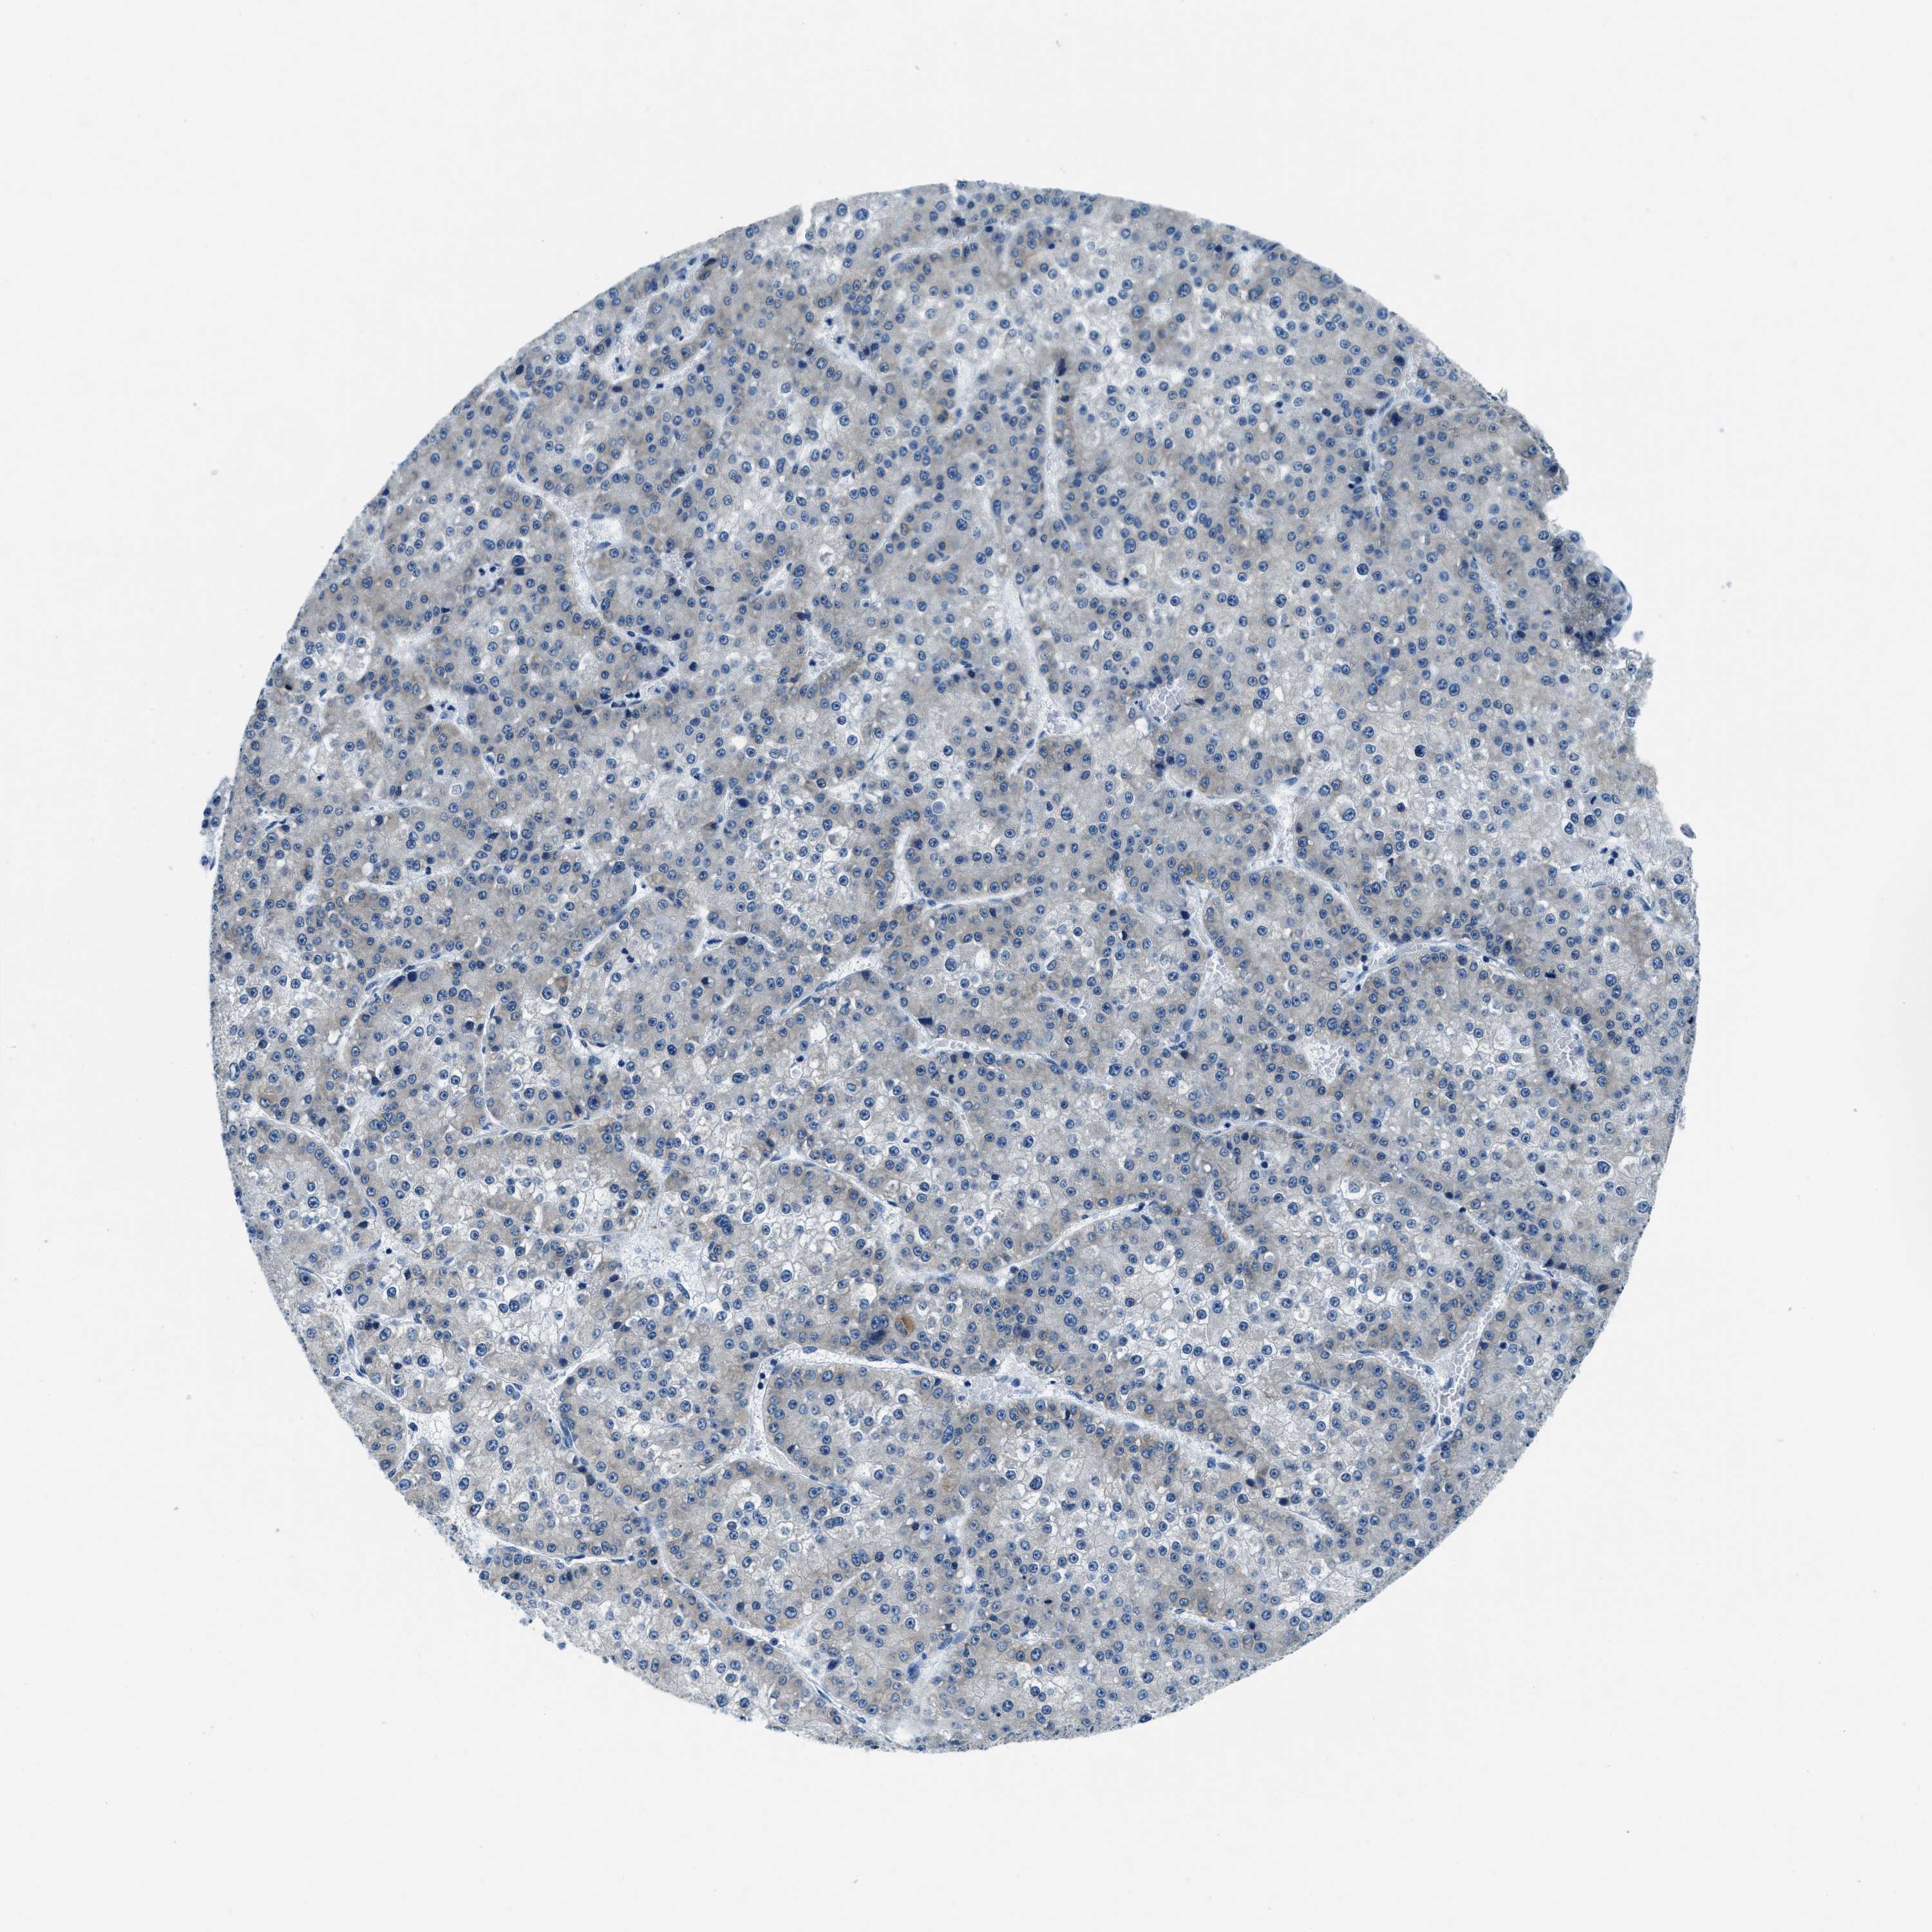

LIVER CANCER - Protein expressioni

A mouse-over function shows sample information and annotation data. Click on an image to view it in a full screen mode. Samples can be filtered based on level of antibody staining by selecting one or several of the following categories: high, medium, low and not detected. The assay and annotation is described here.

Note that samples used for immunohistochemistry by the Human Protein Atlas do not correspond to samples in the TCGA dataset.

Antibody stainingi

Antibody staining in the annotated cell types in the current human tissue is reported as not detected, low, medium, or high, based on conventional immunohistochemistry profiling in selected tissues. This score is based on the combination of the staining intensity and fraction of stained cells.

Each image is clickable and will lead to virtual microscopy that enables deeper exploration of all samples and also displays staining intensity scores, fraction scores and subcellular localization as well as patient and tissue information for each sample.

Antibody HPA013448

Staining

High

Medium

Low

Not detected

Intensity

Strong

Moderate

Weak

Negative

Quantity

>75%

75%-25%

<25%

None

Location

Nuclear

Cytoplasmic/membranous

Cytoplasmic/membranous,nuclear

Cholangiocarcinoma

Carcinoma, Hepatocellular, NOS